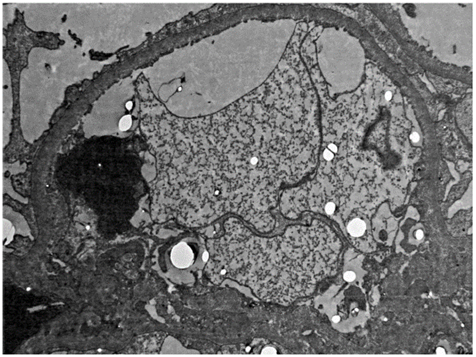

A 22-year-old male patient who had no pathologic antecedents in his medical record presented fever, olfactory amnesia, dysgeusia, diarrhea and anasarca at the time of admission to our healthcare center. After performing a PCR for SARS-CoV-2, the result came back positive. Among the laboratory studies carried out, elevated serum lactate dehydrogenase values (LDH, 274 U/L), hypercholesterolemia (261 mg/dl) and hypoalbuminemia (2.6 g/dl) can be highlighted. By contrast, creatinine test(1 mg/day) and uremia (38 mg/day) levels were normal. Additionally, the virus test panel for human immunodeficiency virus (HIV), hepatitis B (HBV), hepatitis C (HCV), cytomegalovirus (CMV) and Epstein-Barr virus (EBV) was negative. The tests for the immunological markers pANCA, cANCA, ANAS and anti-DNA were negative, and complement component levels were normal: C3 116 mg/dl (88-165 mg/dl) and C4 16.4 mg/dl (14-44 mg/dl). PLA2R antibody was not measured since it was not available. However, severe proteinuria was present (26 g/day). Urotomography revealed normal kidneys and pleural effusion. A diagnosis of pneumonia caused by SARS-CoV-2 and nephrotic syndrome was made. Treatment with furosemide (40 mg/day), enalapril (10 mg/day), spironolactone (25 mg/day) and atorvastatin (10 mg/day) was initiated, and kidney biopsy was performed. Light microscopy revealed eight glomeruli showing glomerulomegaly without any evidence of fibrous or cellular crescents. A pattern of minimal changes in the absence of any remarkable glomerular abnormality was identified, except for one observed glomerulus that presented segmental mesangial proliferation. Furthermore, no abnormalities in the basement membranes, duplication, spicules or double contour were identified. Alterations in the tubules, vessels, and interstice were not observed. Direct immunofluorescence studies revealed no immunoglobulin or complement deposits (Figures 1 and 2). From the ultrastructural point of view, it was possible to demonstrate changes associated with podocyte foot fusion in >80 % of the basal membrane extension, which constituted a diffuse podocytopathy (Figure 3). Two weeks later, the patient showed spontaneously significant proteinuria (0.5 g/dia), edema reduction, as well as negative PCR result for SARS-CoV-2 in a new exam, thus he was discharged.

Note: Electron microscopy showing effacement of podocytes sitting over a basal glomerular membrane.

Source: the authors.

Figure 6 Case 2 - Electron microscopy (glomerulus image)